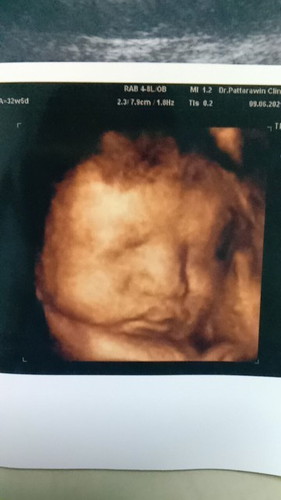

ภาพซาวด์น้อง ปากบนใหญ่ จมูกใหญ่มากเลยค่ะ ออกมาจะเป็นแบบนี้ไหมคะ#ใครมีประสบการณ์

ส่วนมากคลอดมาจะเป็นเหมือนในภาพค่ะ อยู่ที่พ่อแม่อีกค่ะว่าหน้าตาแบบน้องไหมในตอนเด็ก

มันก็ไม่ขนาดนี้หรอกค่ะ มันเหมือนภาพซูมทุกอย่างเลยดูใหญ่เกิน

น่าจะคล้ายๆในภาพเลยค่ะ

ส่วนมากออกมาเหมือนค่ะ